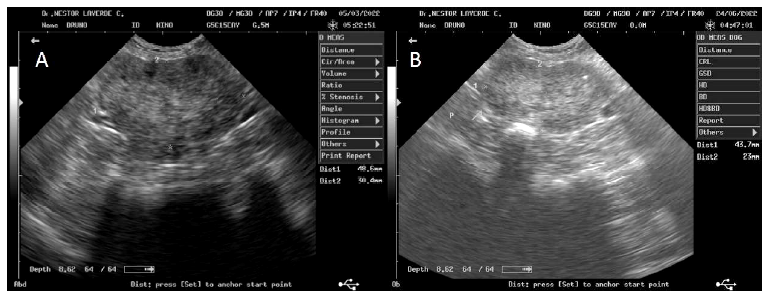

Se tomaron muestras de sangre para hemograma, perfil hepático (alanina aminotransferasa [ALT], fosfatasa alcalina sérica, albúmina, ácidos biliares), y perfil renal (creatinina, nitrógeno ureico en sangre [BUN], calcio, fósforo, ácido úrico).Además, se obtuvo una muestra de orina por cistocentesis para uroanálisis. En el hemograma se encontró trombocitopenia y neutrofilia con desviación a la izquierday y en el uronanálisis se identificó la presencia de espermatozoides, leucocituria (3+) proteinuria (2+) y sangre (2+). Además, se realizó ecografía transabdominal donde se identificaron los testículos retenidos, la próstata aumentada de tamaño, con un parénquima heteroecogénico y microquistes (Figura 2).

Los perros con hiperplasia prostática benigna son propensos a desarrollar hiperplasia prostática benigna quística y prostatitis y, a pesar de que el diagnóstico definitivo de la enfermedad prostática requiere biopsia, se puede realizar un diagnóstico presuntivo de la enfermedad con base en los signos clínicos, la historia, el examen rectal, la citología y los hallazgos ecográficos (Smith, 2008). El diagnóstico de hiperplasia prostática benigna quística del presente caso se basó en los hallazgos ecográficos, los signos sistémicos, las alteraciones hematológicas, las anormalidades del uroanálisis, la palpación rectal y la citología.